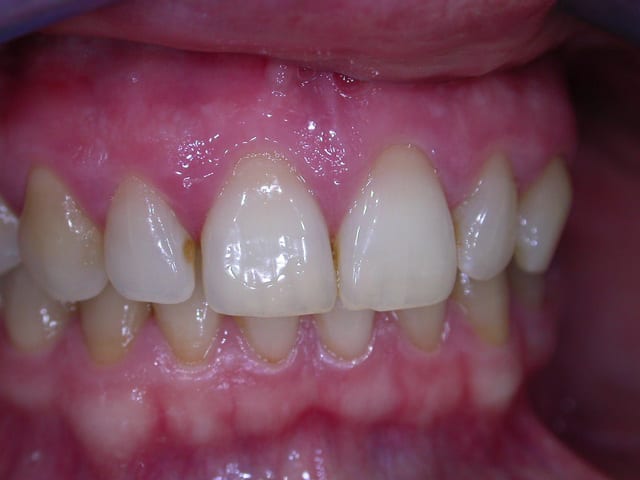

examen buccal .........voir les photos ........après ........ca vient

Bon controle de plaque, pas de tartre ni de colorations, inflammation en palatin seulement...